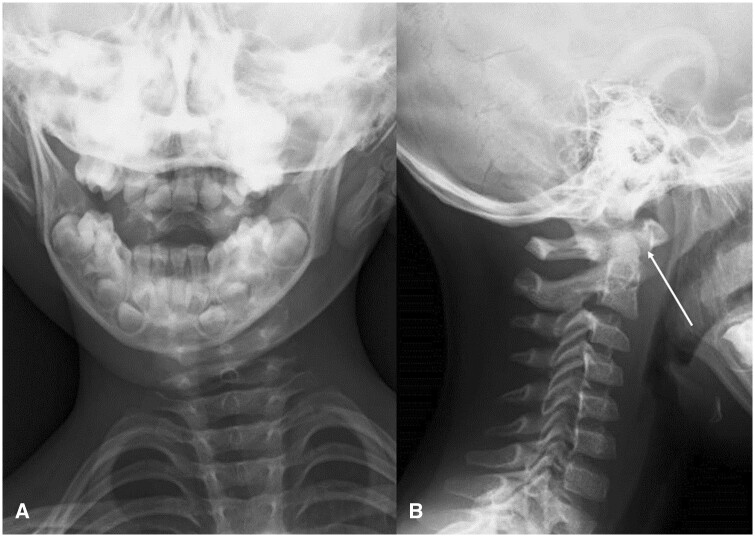

Various respiratory, musculoskeletal, gastrointestinal, neurological, and urinary complications have been reported in Kawasaki disease. Here, we describe a rare case of atlantoaxial rotatory fixation (AARF) associated with incomplete Kawasaki disease. The case is of a healthy 4-year-old Japanese boy who had a high-grade fever, lymphadenopathy, and torticollis diagnosed with incomplete Kawasaki disease. Intravenous high-dose immunoglobulin and oral aspirin quickly resolved his fever and improved his lymphadenopathy, but torticollis remained. On orthopaedic examination, torticollis was observed with a marked restriction of rotation, and an open-mouth anteroposterior cervical radiograph and a CT scan confirmed rotational dislocation at the dens axis (AARF). Cervical collar fixation was immediately started, and the torticollis gradually normalized within a week. AARF is defined as torticollis due to dislocation or subluxation of the atlantoaxial joint. The diagnosis of AARF is difficult with routine plain cervical radiographs in 2 directions alone, and an additional cervical open-mouth anteroposterior radiograph and a CT scan aid the diagnosis. AARF associated with Kawasaki disease is uncommon, and only 24 cases have been reported in the literature. AARF may occur in Kawasaki disease patients with cervical lymphadenopathy. Still, torticollis is often transient and may not be recognized or ignored by family doctors and paediatricians. Reduction of the atlantoaxial joint can often be achieved spontaneously or with conservative treatment such as a collar or neck traction, but treatment is difficult if the diagnosis is delayed. Therefore, family doctors and paediatricians need to suspect the onset of AARF if torticollis is observed during treatment for Kawasaki disease, perform plain cervical radiographs including open-mouth anteroposterior view and a CT scan of the cervical spine, and have orthopaedists immediately intervene to avoid invasive surgery.